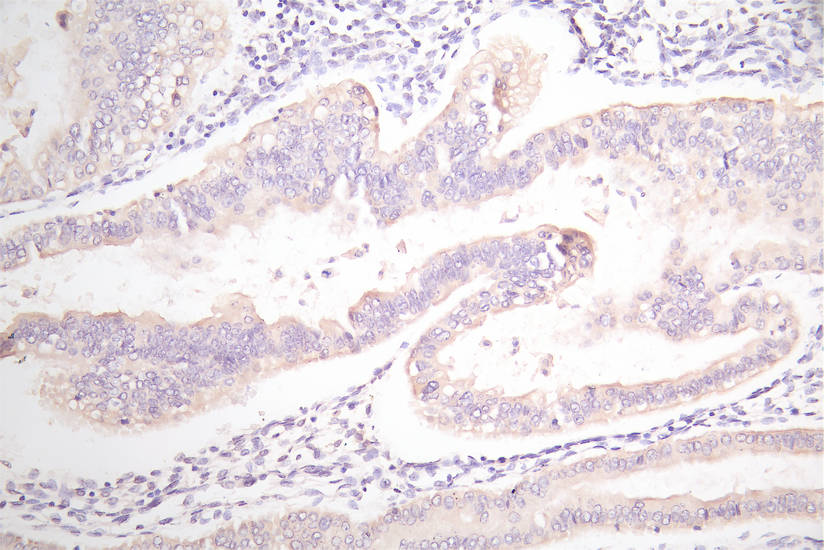

IHC image of CSB-RA007717MA1HU diluted at 1:100 and staining in paraffin-embedded human endometrial cancer performed on a Leica BondTM system. After dewaxing and hydration, antigen retrieval was mediated by high pressure in a citrate buffer (pH 6.0). Section was blocked with 10% normal goat serum 30min at RT. Then primary antibody (1% BSA) was incubated at 4°C overnight. The primary is detected by a Goat anti-Mouse IgG labeled by HRP and visualized using 0.05% DAB.